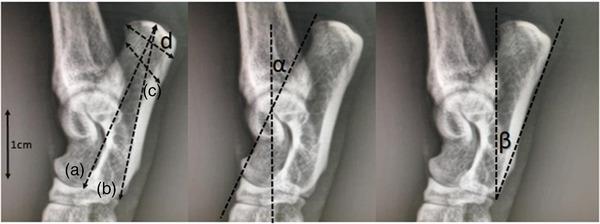

This study examined whether radiographic images measurements of the calcaneus in cats are determinative of sex and breed. For this purpose, radiographic images of 70 cats (37 male and 33 females) of different ages (from one to 18 years) and different breeds (41 mix-breed, 18 Scottish Fold and 11 British Shorthair cats) without orthopaedic problems were used. Right tarsal joint radiographs of these orthopaedically healthy cats were taken. Four linear measurements and two angle values of the calcaneus were obtained from the radiographic images. The MANOVA result showed that the most determining factor between the three groups was the greatest width (p value = 0.001). Calcaneal body length, calcaneal greatest length and calcaneal shortest depth were higher in mix-breed cats. Calcaneal tuber length was higher in Scottish Fold cats. The only statistically significant difference between Scottish Fold and British Shorthair was in the calcaneal tuber length (p value = 0.04). In the comparison made between the sexes regardless of species, the linear measurements in males were higher than in females. It was determined that these parameters are statistically significant in terms of sex differentiation in cats. Dorsal and plantar calcaneal angles are not sex determinants in cats. The effect of age on other measurements was analysed by correlation test. However, the effect of age on the measurements was not statistically significant. Mix-breed cats were examined in four groups according to their colour (grey, black-white, yellow, tri-colour). No statistically significant difference was found between calcaneal measurements of cats with different skin colour genotypes. In this study, calcaneus measurements were both determinative between breeds and sexes in cats.

本研究旨在探讨猫的跟骨 X 光片测量值是否可用于确定性别和品种。为此,我们使用了 70 只不同年龄(1 至 18 岁)和不同品种(41 只混种、18 只苏格兰折耳猫和 11 只英国短毛猫)的无骨科问题的猫的 X 光片。对这些骨骼健康的猫进行了右跗关节 X 光检查。从 X 光片中获取了跟骨的四个线性测量值和两个角度值。多变量方差分析(MANOVA)的结果表明,三个组之间最具决定性的因素是最大宽度(p 值=0.001)。混种猫的跟骨体长、跟骨最大长度和跟骨最短深度较高。苏格兰折耳猫的跟骨结节长度较高。苏格兰折耳猫和英国短毛猫之间唯一具有统计学意义的差异是在跟骨结节长度上(p 值=0.04)。在不论种属而仅比较性别的情况下,雄性的线性测量值高于雌性。确定这些参数在猫的性别分化方面具有统计学意义。背侧和跖侧跟骨角度不是猫的性别决定因素。相关性检验分析了年龄对其他测量值的影响。然而,年龄对测量值的影响没有统计学意义。根据毛色(灰色、黑白、黄色、三色)将混种猫分为四组进行检查。不同毛色基因型猫的跟骨测量值之间没有统计学差异。在这项研究中,跟骨测量值在猫的品种和性别之间均具有决定性。